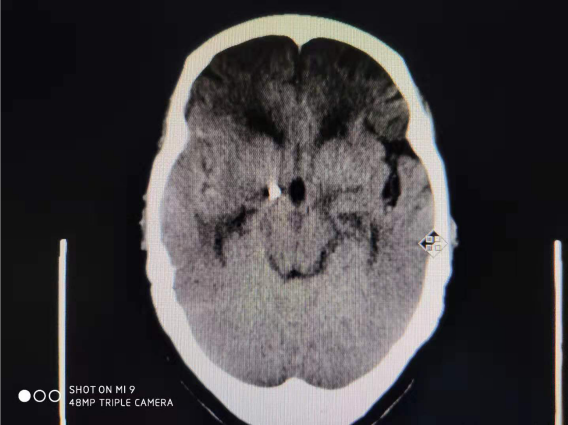

病例二:患者老年女性,以突发头痛收入我科,头颅CT提示:蛛网膜下腔出血,头颅CTA提示:颅内动脉瘤。急诊行脑血管造影及动脉瘤栓塞,术后患者恢复理想,已治愈出院。